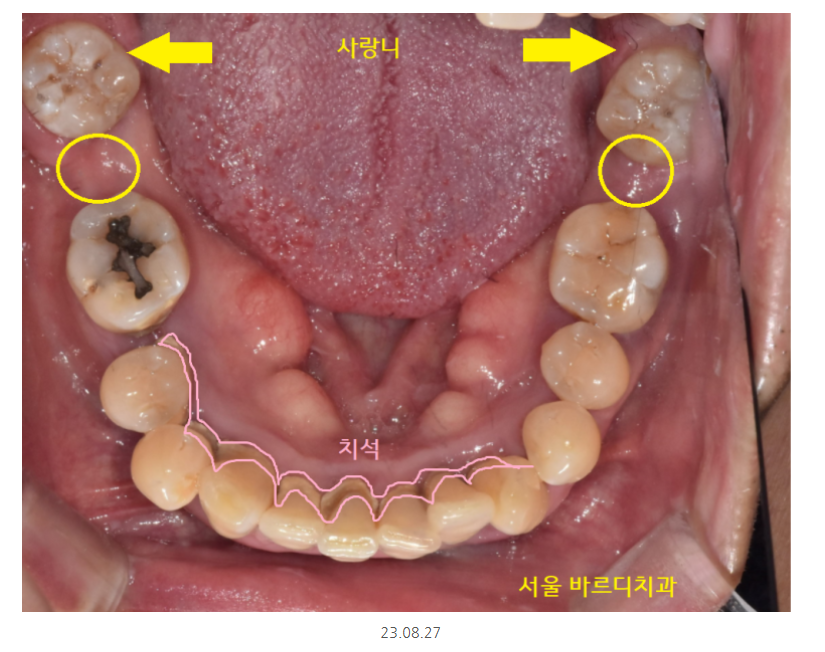

그동안 치아 상태는 이런 모습이셨어요.

어금니는 없고

식사는 하셔야하니까

7개월동안 임시틀니로 식사 하실 수 있게 했습니다.

얼마나 불편하셨겠어요.

매일 삼시세끼 밥을 먹는데

어금니 없는채로 7개월을 지내셨으니요..

정기점검때에도 흡연 계속 하시냐..

확인했던 기억이 있네요.

임플란트 오래 쓰실 수 있게 말이죠!

잇몸 청소 주기적으로 하는것 외에도

흡연이 구강에 미치는 영향

알려드리는 것이 저의 역할이니까요~